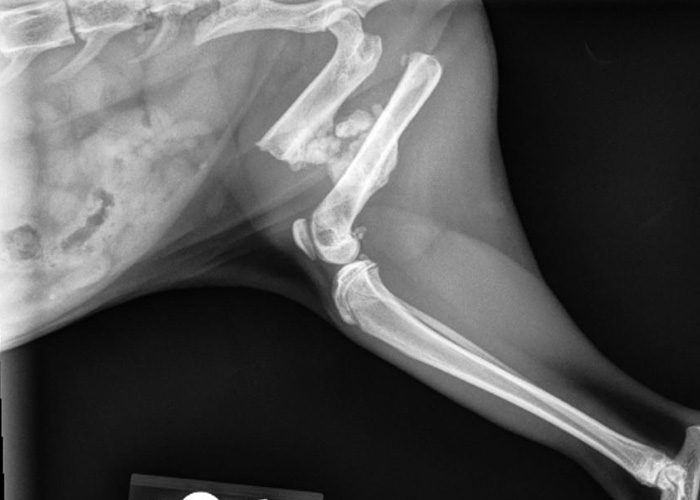

Puppy suffered gunshot wound at former home in Mississippi

The source shelter in Mississippi confirmed that Biscuit’s wound was the result of a gunshot.

His former owner brought the puppy to the shelter for his safety, saying that their neighbor was discharging a firearm at the property, and that a bullet had grazed the puppy’s head.